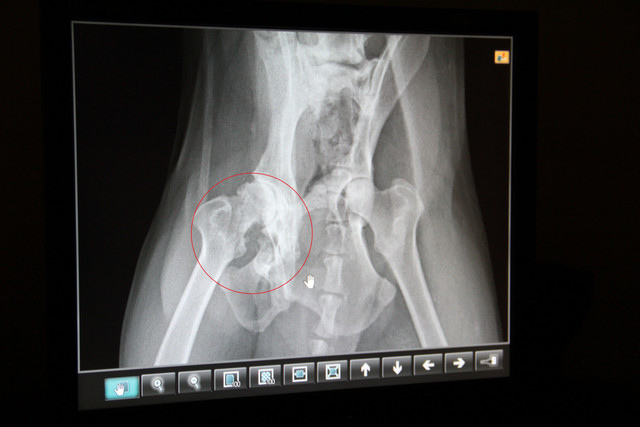

我們總共拍了三張X片,終於發現為什麼一碰小黑的身體,他就氣得想咬人的原因了!

小黑有兩個大問題:

一、小黑右腳的股骨頭已經增生變大,與髖關節窩造成摩擦,也就是我們說的髖關節發育不全症。

二、從X光片的紅色圈圈部份,看的出來小黑的骨盆已經破裂,傾斜了。所以小黑整個背部可以說已經成為一個s型。

邱醫師拿了一個模型跟我解說,

你可以看到他左手指頭的位置,有兩個圓圓的洞,這就是閉瑣孔。

對照上方小黑的X光片,小黑的右邊骨盆的閉鎖孔已經消失了,這代表小黑右邊的整個骨盆曾遭受過外力的撞擊而粉碎。

現在自體的癒合讓他的骨盆自行黏合成為一整陀骨頭,造成他現在的身體上下左右都成為一個S型。這也是運氣不錯,骨盆狀況更糟的,不僅無法站立,行走,甚至連排便都會有問題。

這也是小黑他不願意讓人碰觸他身體的原因,因為這是很疼痛的傷口。

邱醫師的建議是先為小黑做右腳髖關節手術,左腳應該可以先不要動,至於骨盆傾斜的問題,因為已經癒合了,也就沒有辦法治療了。